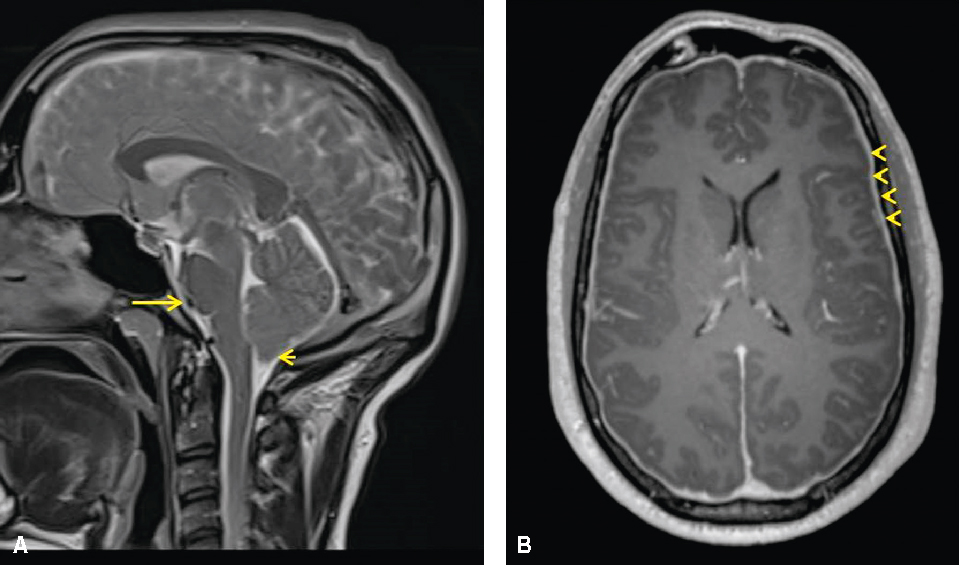

• • L’IRM peut montrer des anomalies morphologiques en rapport avec le déplacement cranio-caudal de l’encéphale (aspect de ptose amygdalienne cérébelleuse, effacement des citernes prépontiques et chiasmatiques) et une prise de contraste diffuse et régulière des pachymé-ninges (fig. 24.1).

Les images IRM montrent des signes de syndrome post-ponction lombaire avec hypotension du LCS, indiquant des anomalies dans les structures cérébrales dues à la perte de LCS.

Fig. 24.1 Figure Patient présentant un syndrome post-ponction lombaire avec hypotension du LCS.

IRM cérébrale. A. Séquence T2 (coupe sagittale). B. Séquence T1 avec gadolinium (coupe axiale). Effacement de la citerne prépontique (flèche longue), discrète ptose de l’amygdale cérébelleuse (flèche courte), prise de contraste diffuse et régulière des pachyméninges (têtes de flèches).